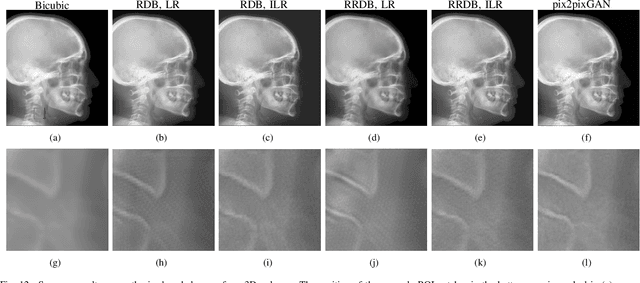

Abstract:Due to the lack of standardized 3D cephalometric analytic methodology, 2D cephalograms synthesized from 3D cone-beam computed tomography (CBCT) volumes are widely used for cephalometric analysis in dental CBCT systems. However, compared with conventional X-ray film based cephalograms, such synthetic cephalograms lack image contrast and resolution. In addition, the radiation dose during the scan for 3D reconstruction causes potential health risks. In this work, we propose a sigmoid-based intensity transform that uses the nonlinear optical property of X-ray films to increase image contrast of synthetic cephalograms. To improve image resolution, super resolution deep learning techniques are investigated. For low dose purpose, the pixel-to-pixel generative adversarial network (pix2pixGAN) is proposed for 2D cephalogram synthesis directly from two CBCT projections. For landmark detection in the synthetic cephalograms, an efficient automatic landmark detection method using the combination of LeNet-5 and ResNet50 is proposed. Our experiments demonstrate the efficacy of pix2pixGAN in 2D cephalogram synthesis, achieving an average peak signal-to-noise ratio (PSNR) value of 33.8 with reference to the cephalograms synthesized from 3D CBCT volumes. Pix2pixGAN also achieves the best performance in super resolution, achieving an average PSNR value of 32.5 without the introduction of checkerboard or jagging artifacts. Our proposed automatic landmark detection method achieves 86.7% successful detection rate in the 2 mm clinical acceptable range on the ISBI Test1 data, which is comparable to the state-of-the-art methods. The method trained on conventional cephalograms can be directly applied to landmark detection in the synthetic cephalograms, achieving 93.0% and 80.7% successful detection rate in 4 mm precision range for synthetic cephalograms from 3D volumes and 2D projections respectively.